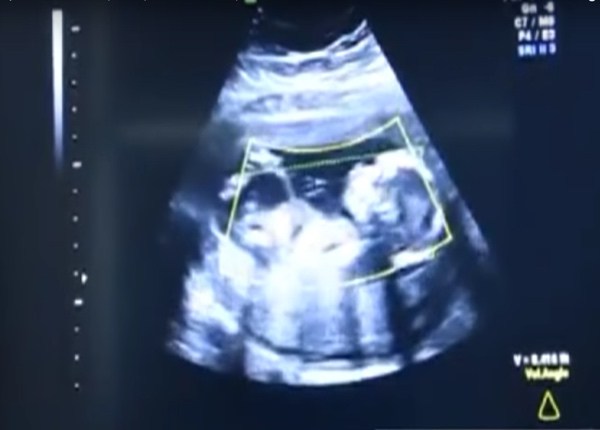

Οι γιατροί προέβησαν σε ενδελεχή εξέταση και μετά βίας μπορούσαν να πιστέψουν στα μάτια τους. Το μωρό δεν αναπτυσσόταν στη μήτρα της μητέρας, αλλά στην κοιλιακή κοιλότητα! Αυτή η σπάνια πάθηση είναι μια μορφή της έκτοπης κύησης, κατά με την οποία το έμβρυο αναπτύσσεται έξω από τη μήτρα στην περιοχή της κοιλιάς. Αυτές οι εγκυμοσύνες έχουν πολύ χαμηλό ποσοστό επιβίωσης, αλλά, σε σπάνιες περιπτώσεις, μπορεί να γεννηθεί ένα υγιές μωρό.

Οι γιατροί ετοιμάστηκαν αμέσως για επείγουσα εγχείρηση. Μια επιτυχημένη εγκυμοσύνη στη κοιλιακή κοιλότητα είναι εξαιρετικά σπάνια και επικίνδυνη. Μόνο ελάχιστες περιπτώσεις είναι γνωστές σε όλο τον κόσμο, με το παιδί να έχει γεννηθεί υγιές. Για να έρθει με ασφάλεια το μωρό στον κόσμο δεν υπήρχε άλλη επιλογή εκτός από το να εκτελέσουν καισαρική τομή.